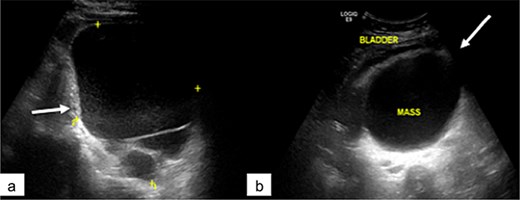

Pelvic MRI was performed for further characterization. It demonstrated a well-circumscribed, multiloculated presacral mass. The lesion appeared hypointense on T1-weighted images and hyperintense on T2-weighted sequences. It contained cystic areas with high signal intensity on both T1 and T2 sequences, as well as thick septations that showed no enhancement following gadolinium administration. The mass displaced the uterus and bladder anteriorly and was clearly separated from both ovaries, which appeared normal in morphology and signal intensity (Fig. 2).

Pelvic MRI. Axial (a), sagittal (b), and coronal (c) T2-weighted images, and sagittal T1-weighted image showing a large multiloculated sacrococcygeal mass containing cystic areas with low T1 signal and high T2 signal (arrow), hemorrhagic components, and fatty components with high T1 and T2 signal (asterisk). No diffusion restriction or contrast enhancement is observed after gadolinium administration.

No signs of local invasion or malignant transformation were identified.